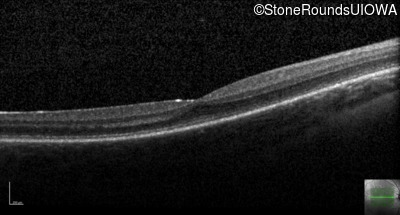

The clinical features supporting the diagnosis of incomplete achromatopsia in this patient include: nystagmus noticed in the first year of life; reduced acuity, poor color vision, a normal fundus appearance, a normal OCT, normally sighted parents and absence of a similarly affected male elsewhere in his mother's family.